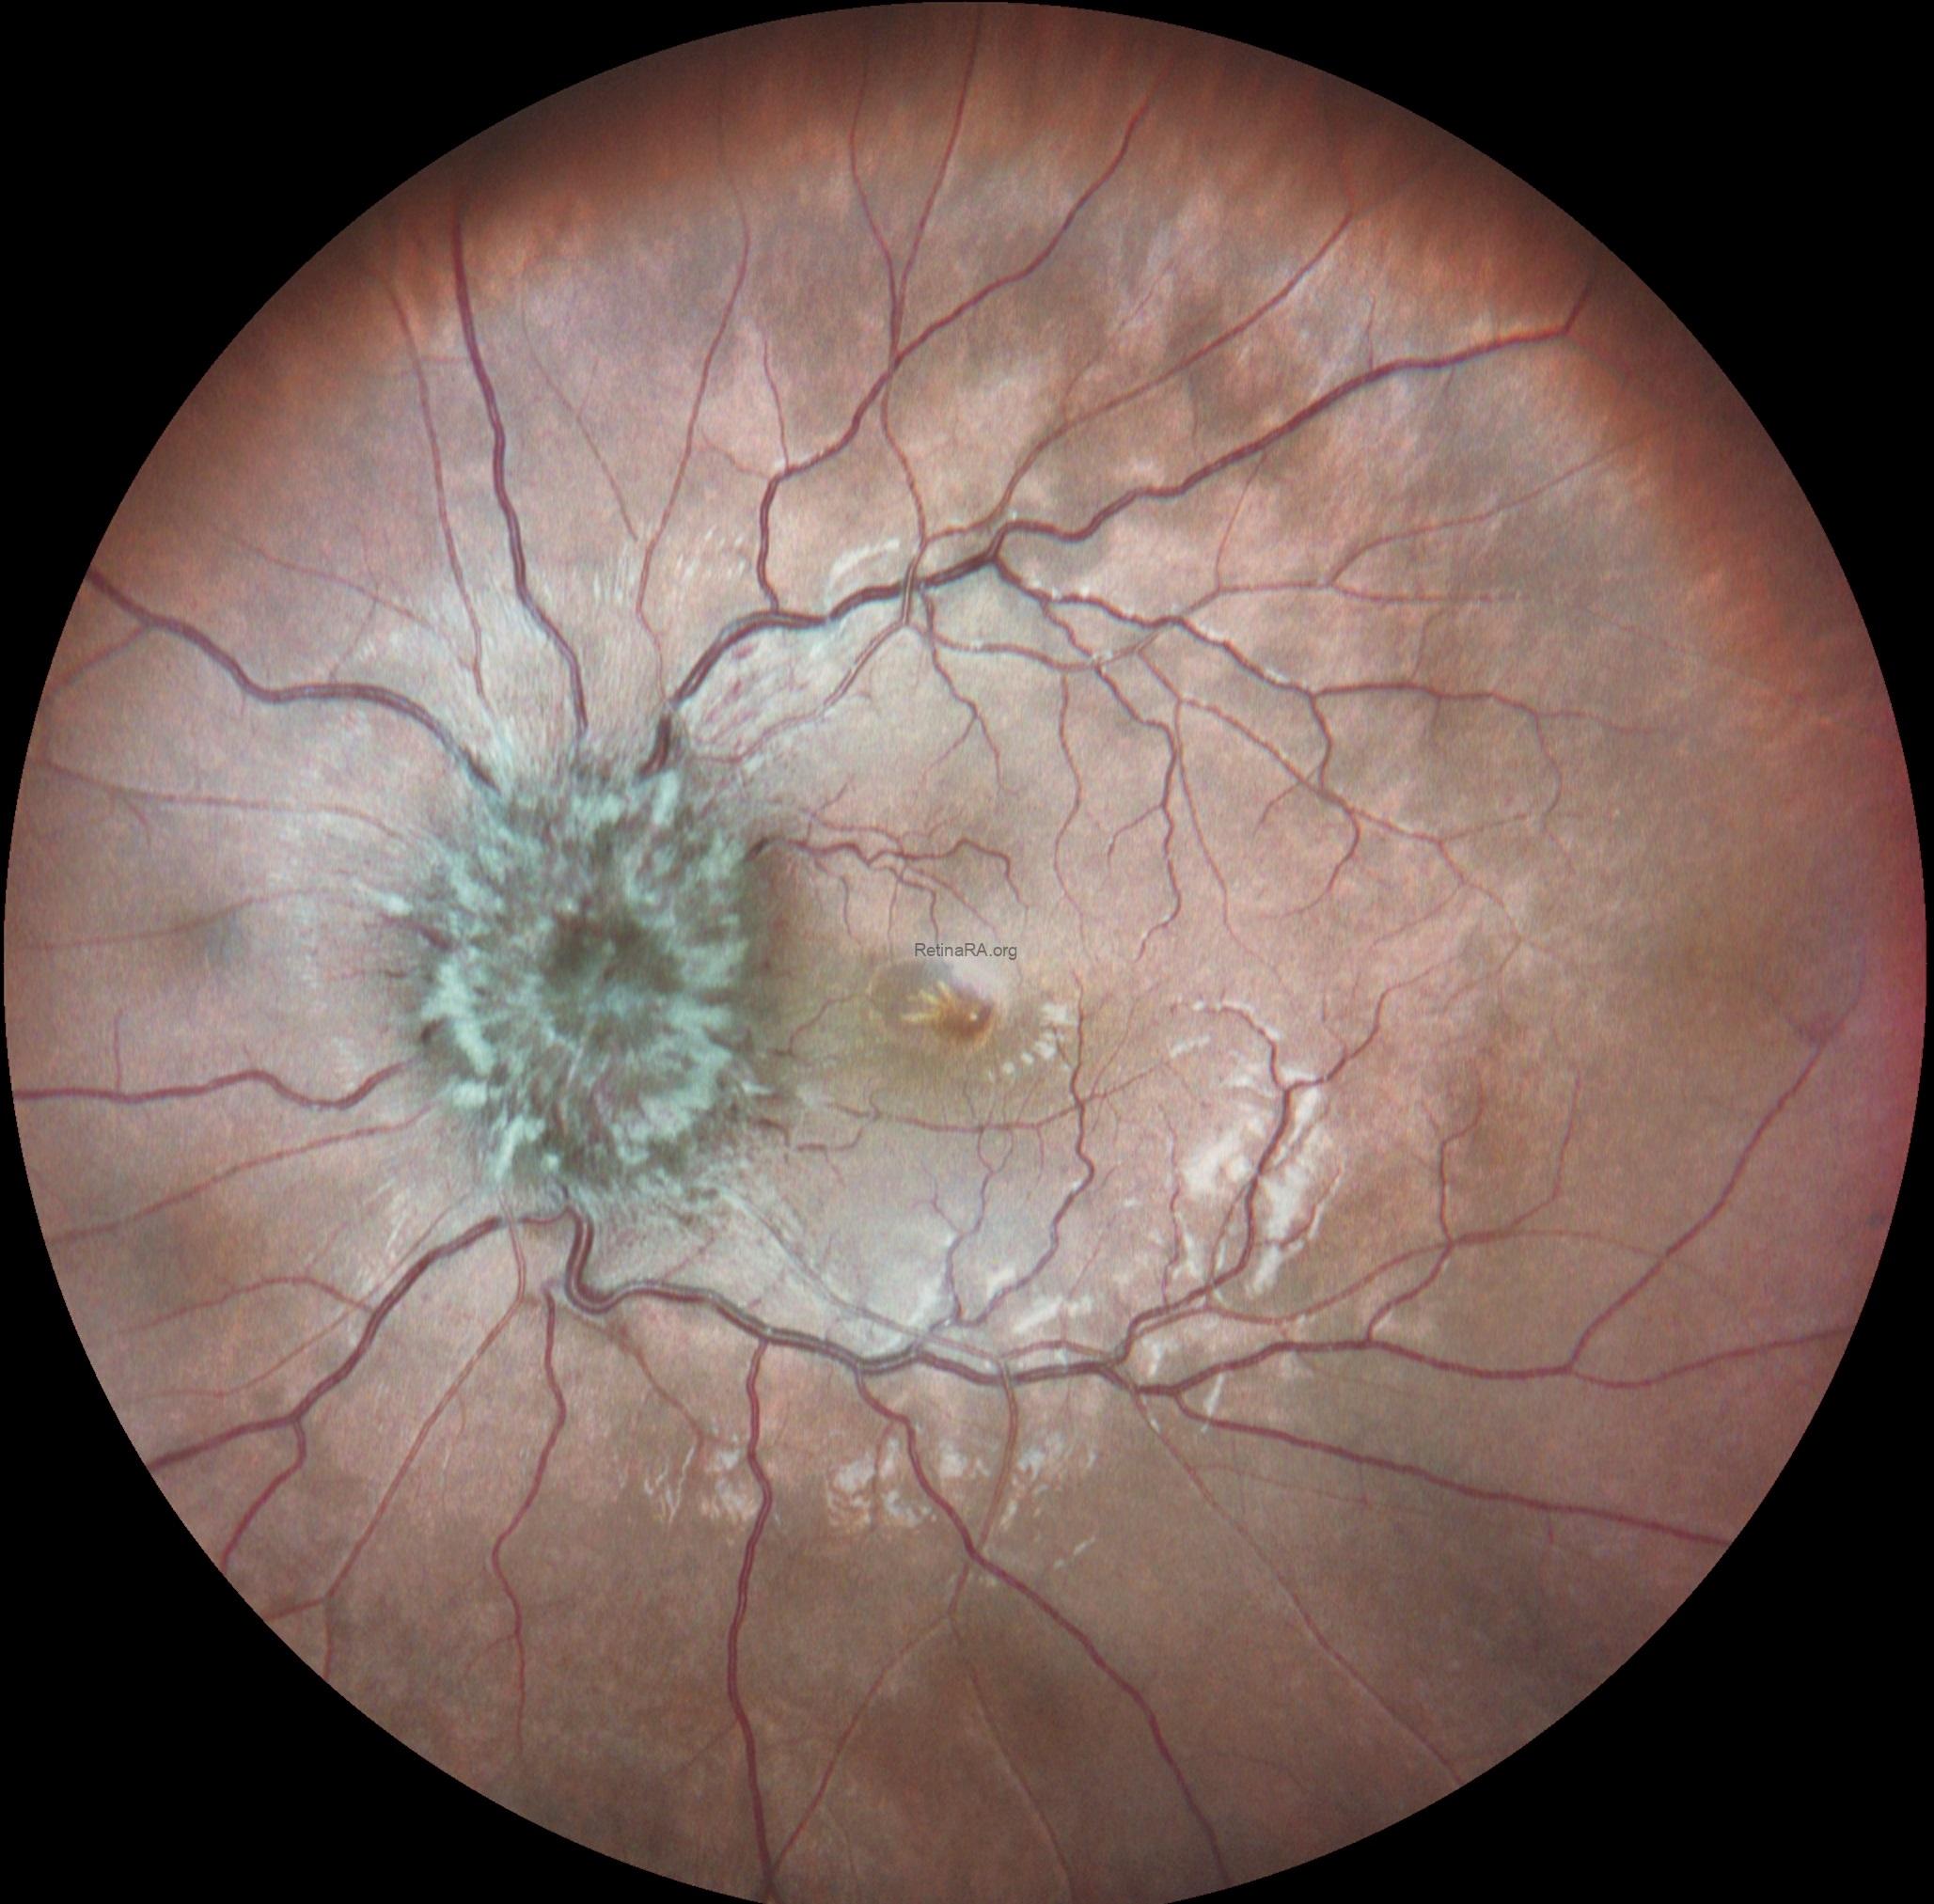

Multicolor and infrared fundus images revealed bilateral severe optic disc swelling, elevation of the disc with blurred margins, smoothly demarcated peripapillary halo, optic nerve head hyperemia, peripapillary hemorrhages, and obscuration of cup and major vessel (Grade 5 according to Frisén Scale).

Based on the optic disc appearence, the patient was diagnosed as severe papilledema and consulted to the neurology department. After neurological asessment including craniyal computed tomography the patient was diagnosed as glioblastoma multiforme.